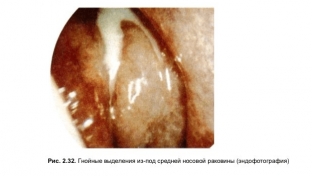

Діагностичний процес гострого етмоїдиту не є складним і ґрунтується насамперед на скаргах пацієнта та характерній клінічній картині захворювання. За допомогою риноскопії вдається побачити набряк та гіперемію слизової оболонки середньої носової раковини, а також слизово-гнійні виділення у носових ходах. При ендоскопічному дослідженні, залежно від того, з передніх осередків або нюхової щілини виходять гнійні виділення, можна встановити відповідно переднім або заднім є етмоїдит. Але найбільш інформативним методом дослідження при гострому етмоїдиті є рентгенографія або комп'ютерна томографія, що дозволяє побачити затемнення гратчастих осередків, що підтверджує діагноз.